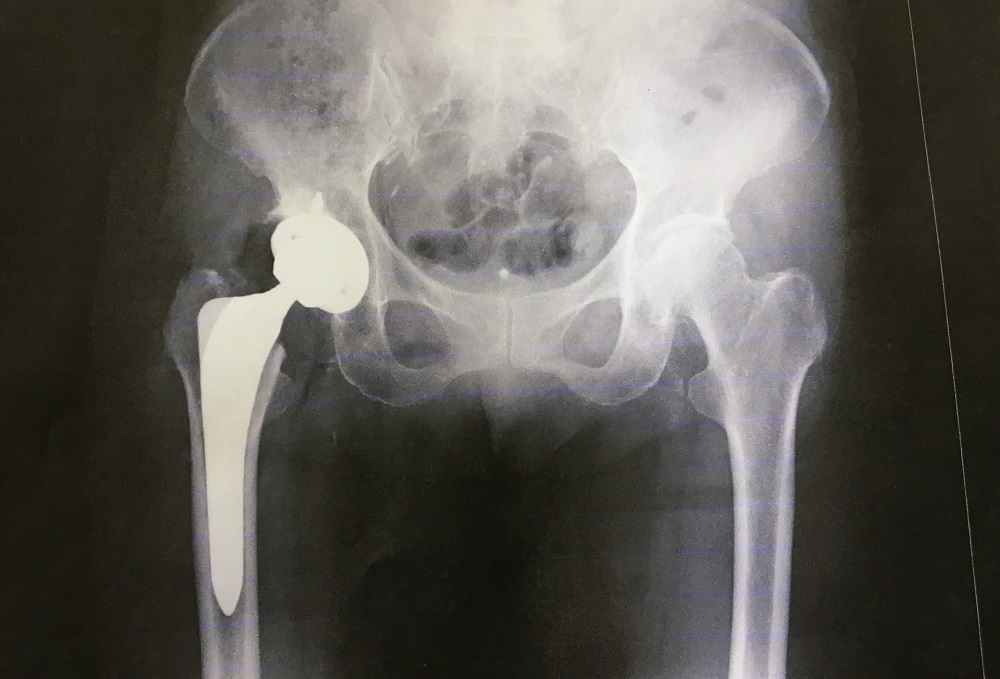

股関節の疾患

-

股関節痛

股関節周辺の痛みを指し、変形性股関節症、関節リウマチ、大腿骨頭壊死、大腿骨頚部骨折などが原因となります。

大腿骨頭壊死

大腿骨の上端(骨頭)への血流が悪くなり、骨が壊死する病気です。壊死した部分がつぶれると強い痛みが出ます。原因不明の「特発性」と、外傷などによる「症候性」に分類されます。

大腿骨近位部骨折

大腿骨の付け根付近で起こる骨折で、主に大腿骨頸部や転子部で発生します。60代以降に増加し、特に骨粗しょう症の方に多く見られます。寝たきりの原因になることもあり、注意が必要です。